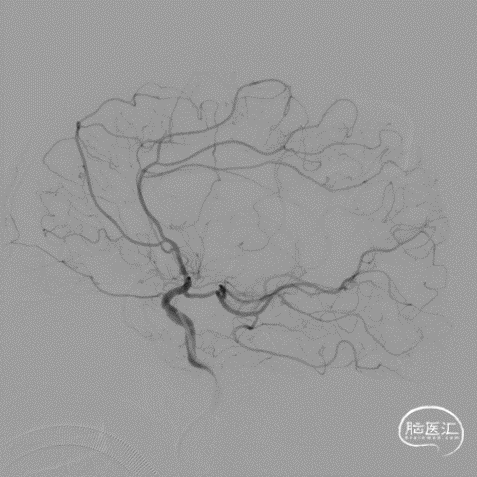

脑血管造影:右侧大脑中动脉M1段闭塞,代偿不足。

选取工作角度造影,测量病变长度。

微导丝辅助微导管通过闭塞段,以赛诺神畅Neuro LPS-1.5-15mm球囊分次扩张闭塞段。

球扩后造影见闭塞段恢复正向血流M1段远端夹层表现。

最后工作位造影和正侧位造影,右侧大脑中动脉区域血流恢复,灌注满意。